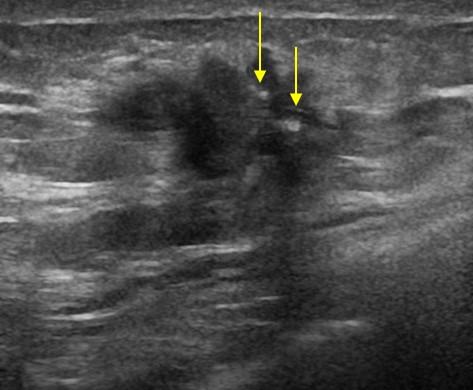

Ung thư vú

Ung thư vú - Ảnh 2

» Thông tin: Nữ giới – 52 tuổi.

» Lâm sàng: Khối tuyến vú.